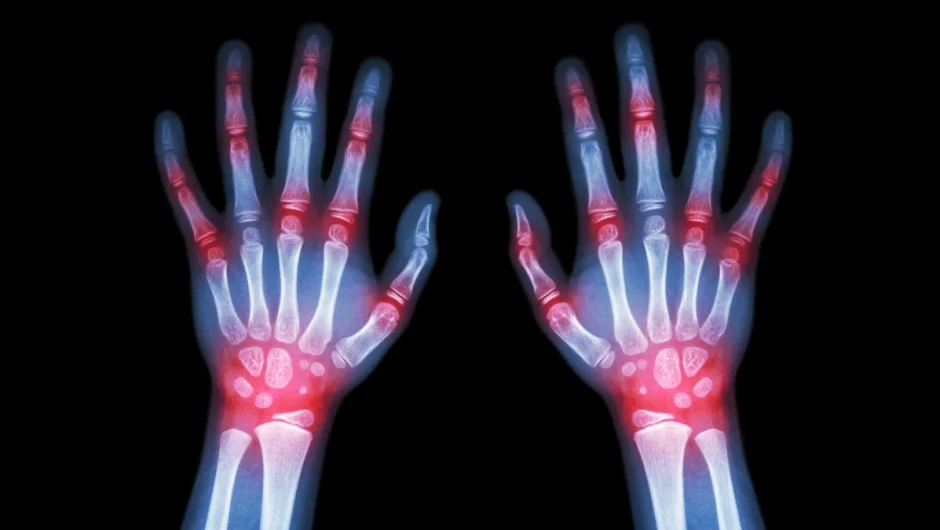

Η Ρευματοειδής Αρθρίτιδα (ΡΑ) χαρακτηρίζεται από πρωινή δυσκαμψία, πρήξιμο και πόνο των αρθρώσεων, αλλά και την πιθανότητα προσβολής άλλων οργάνων,…